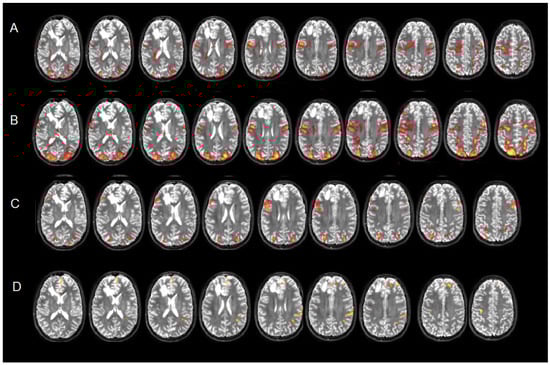

What Can Neurosurgical Pediatric Populations Do in Functional Magnetic Resonance Imaging? Brain Activity Mapping Before Intervention Tasks, a Retrospective Study

by Ilaria Guarracino, Marta Maieron, Serena D’Agostini, Miran Skrap, Paola Cogo, Tamara Ius and Barbara Tomasino

Background/Objectives: Performing presurgical functional magnetic resonance imaging (fMRI) mapping in young patients is considered a challenge for clinicians, as fMRI maps are the sole source of information about the functional organization of cognitive functions/areas, especially when an awake craniotomy is not possible, [...] Read more.

Background/Objectives: Performing presurgical functional magnetic resonance imaging (fMRI) mapping in young patients is considered a challenge for clinicians, as fMRI maps are the sole source of information about the functional organization of cognitive functions/areas, especially when an awake craniotomy is not possible, as is often the case for pediatric populations. The literature on the fMRI tasks used in pediatric populations with brain injuries shows a certain heterogeneity in the approaches (task-based or resting states) and tasks, with a preference for motor/language mapping: tasks assessing extra-language functions are lacking. Methods: We have designed fMRI tasks focused on language and extra-language functions, which can be easily be applied when clinicians need to perform presurgical mapping. We present a retrospective case series of 17 patients. Results: Seventeen young patients (13.4 ± 2.8 years; range 7–16) were included in the study, for whom fMRI was performed. All underwent successful fMRI mapping by completing fMRI tasks selected based on their lesion site. The number of tasks performed by each patient significantly correlated with their age (r(17) = 0.561, p = 0.019). The patients tolerated the assessment and had good motion control: their movement parameters were minimal (range of rotation of −0.015–0.01 degrees; range of translation of −0.8–0.2 mm). The most administered fMRI tasks were tongue motor localizer (60%) and object naming (70%), with some patients performing extra-language function mapping involving visuo-spatial processing, selective attention, memory, and inhibition. Conclusions: This is an exploratory study given the sample size. fMRI measurements were considered feasible, as patients were able to complete the tasks under clinically realistic conditions. We discuss the clinical implication/usefulness of administering tasks for a personalized functional assessment of the young patient before surgery. Full article

Figure 1